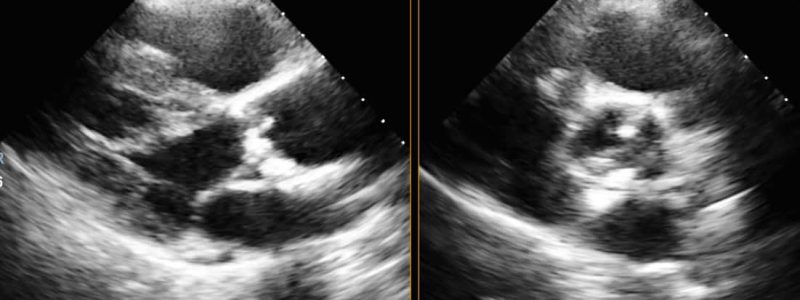

- Ich biete alle in der Praxis möglichen kardiologischen Untersuchungen und Möglichkeiten der Nachkontrolle inklusive implantierte elektronischer Geräte mit moderner Technologie an und arbeite mit allen kardiologischen Kliniken der Schweiz und dem Röngteninstitut IMAMED für weitergehende Untersuchungen zusammen. Ich investiere auch in technologische Fortschritte, die eine bessere oder weniger belastende Diagnostik erlauben. Aktuell habe ich das neueste Echokardiografiegerät von Philips als einer der Ersten in der Schweiz erworben (EPIC CVx). Ausserdem ist die Auswertung von Langzeit-EKG’s auf den neuesten Stand gebracht worden.